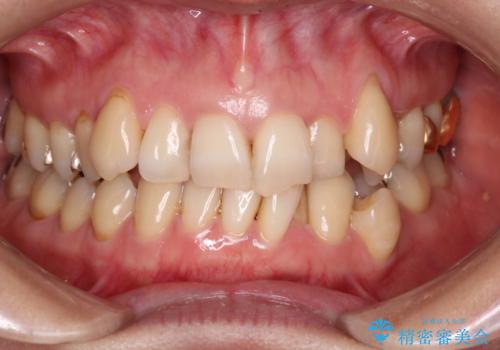

- 上下の歯の凸凹を主訴に来院されました。

他院では抜歯+ワイヤー矯正の提案をされているとのことでした。

当院での検査にて非抜歯+インビザライン矯正を提案させていただき治療を行なっております。